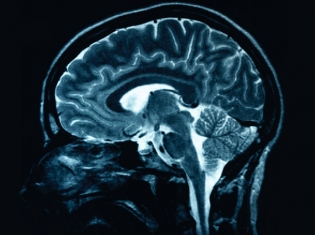

(RxWiki News) With the prevalence of strokes, diagnostic tools to predict risk are becoming more useful than ever. A simple ultrasound test could help identify individuals at a high risk of stroke.

If the ultrasound revealed asymptomatic carotid stenosis, a narrowing of the carotid artery in the neck, which is the main artery between the heart and brain, patients are at a higher stroke risk.

As part of the study, 435 patients with asymptomatic carotid stenosis were followed for two years. All of the participants received ultrasounds of the carotid artery and blood vessels to the brain to investigate whether two markers for high risk of stroke were present. Those markers include blood clots passing into the brain and carotid plaque.